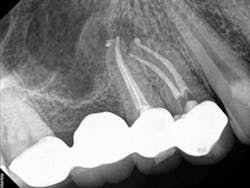

A 50-year-old male presented to my office on referral from his general dentist for evaluation of a large, periapical radiolucency relating to Nos. 4 and 5. Appropriate bitewing and peri-apical radiographs were taken (Fig. 1) for initial evaluation. After all clinical testing was performed, the recommendation was made to take a narrow-field CBCT image of teeth Nos. 4 and 5 (Figs. 2 and 3). The axial view reveals an untreated buccal canal on tooth No. 4 and potential separated instruments in both the buccal and palatal canal space of No. 5. Tooth No. 5 (Fig. 3) shows a short fill, meaning the entire canal space may not have been properly shaped and cleaned. With the three-dimensional images, we now have a better understanding of why these teeth present with post-treatment disease. This information is extremely important when discussing etiology and prognosis with our patients. It will also financially benefit the patient to maintain his existing fixed prosthesis with conservative retreatment of Nos. 4 and 5, knowing that we should have a high degree of long-term success seeing a clear etiology of the post-treatment disease.

Fig. 3: CBCT sagittal view